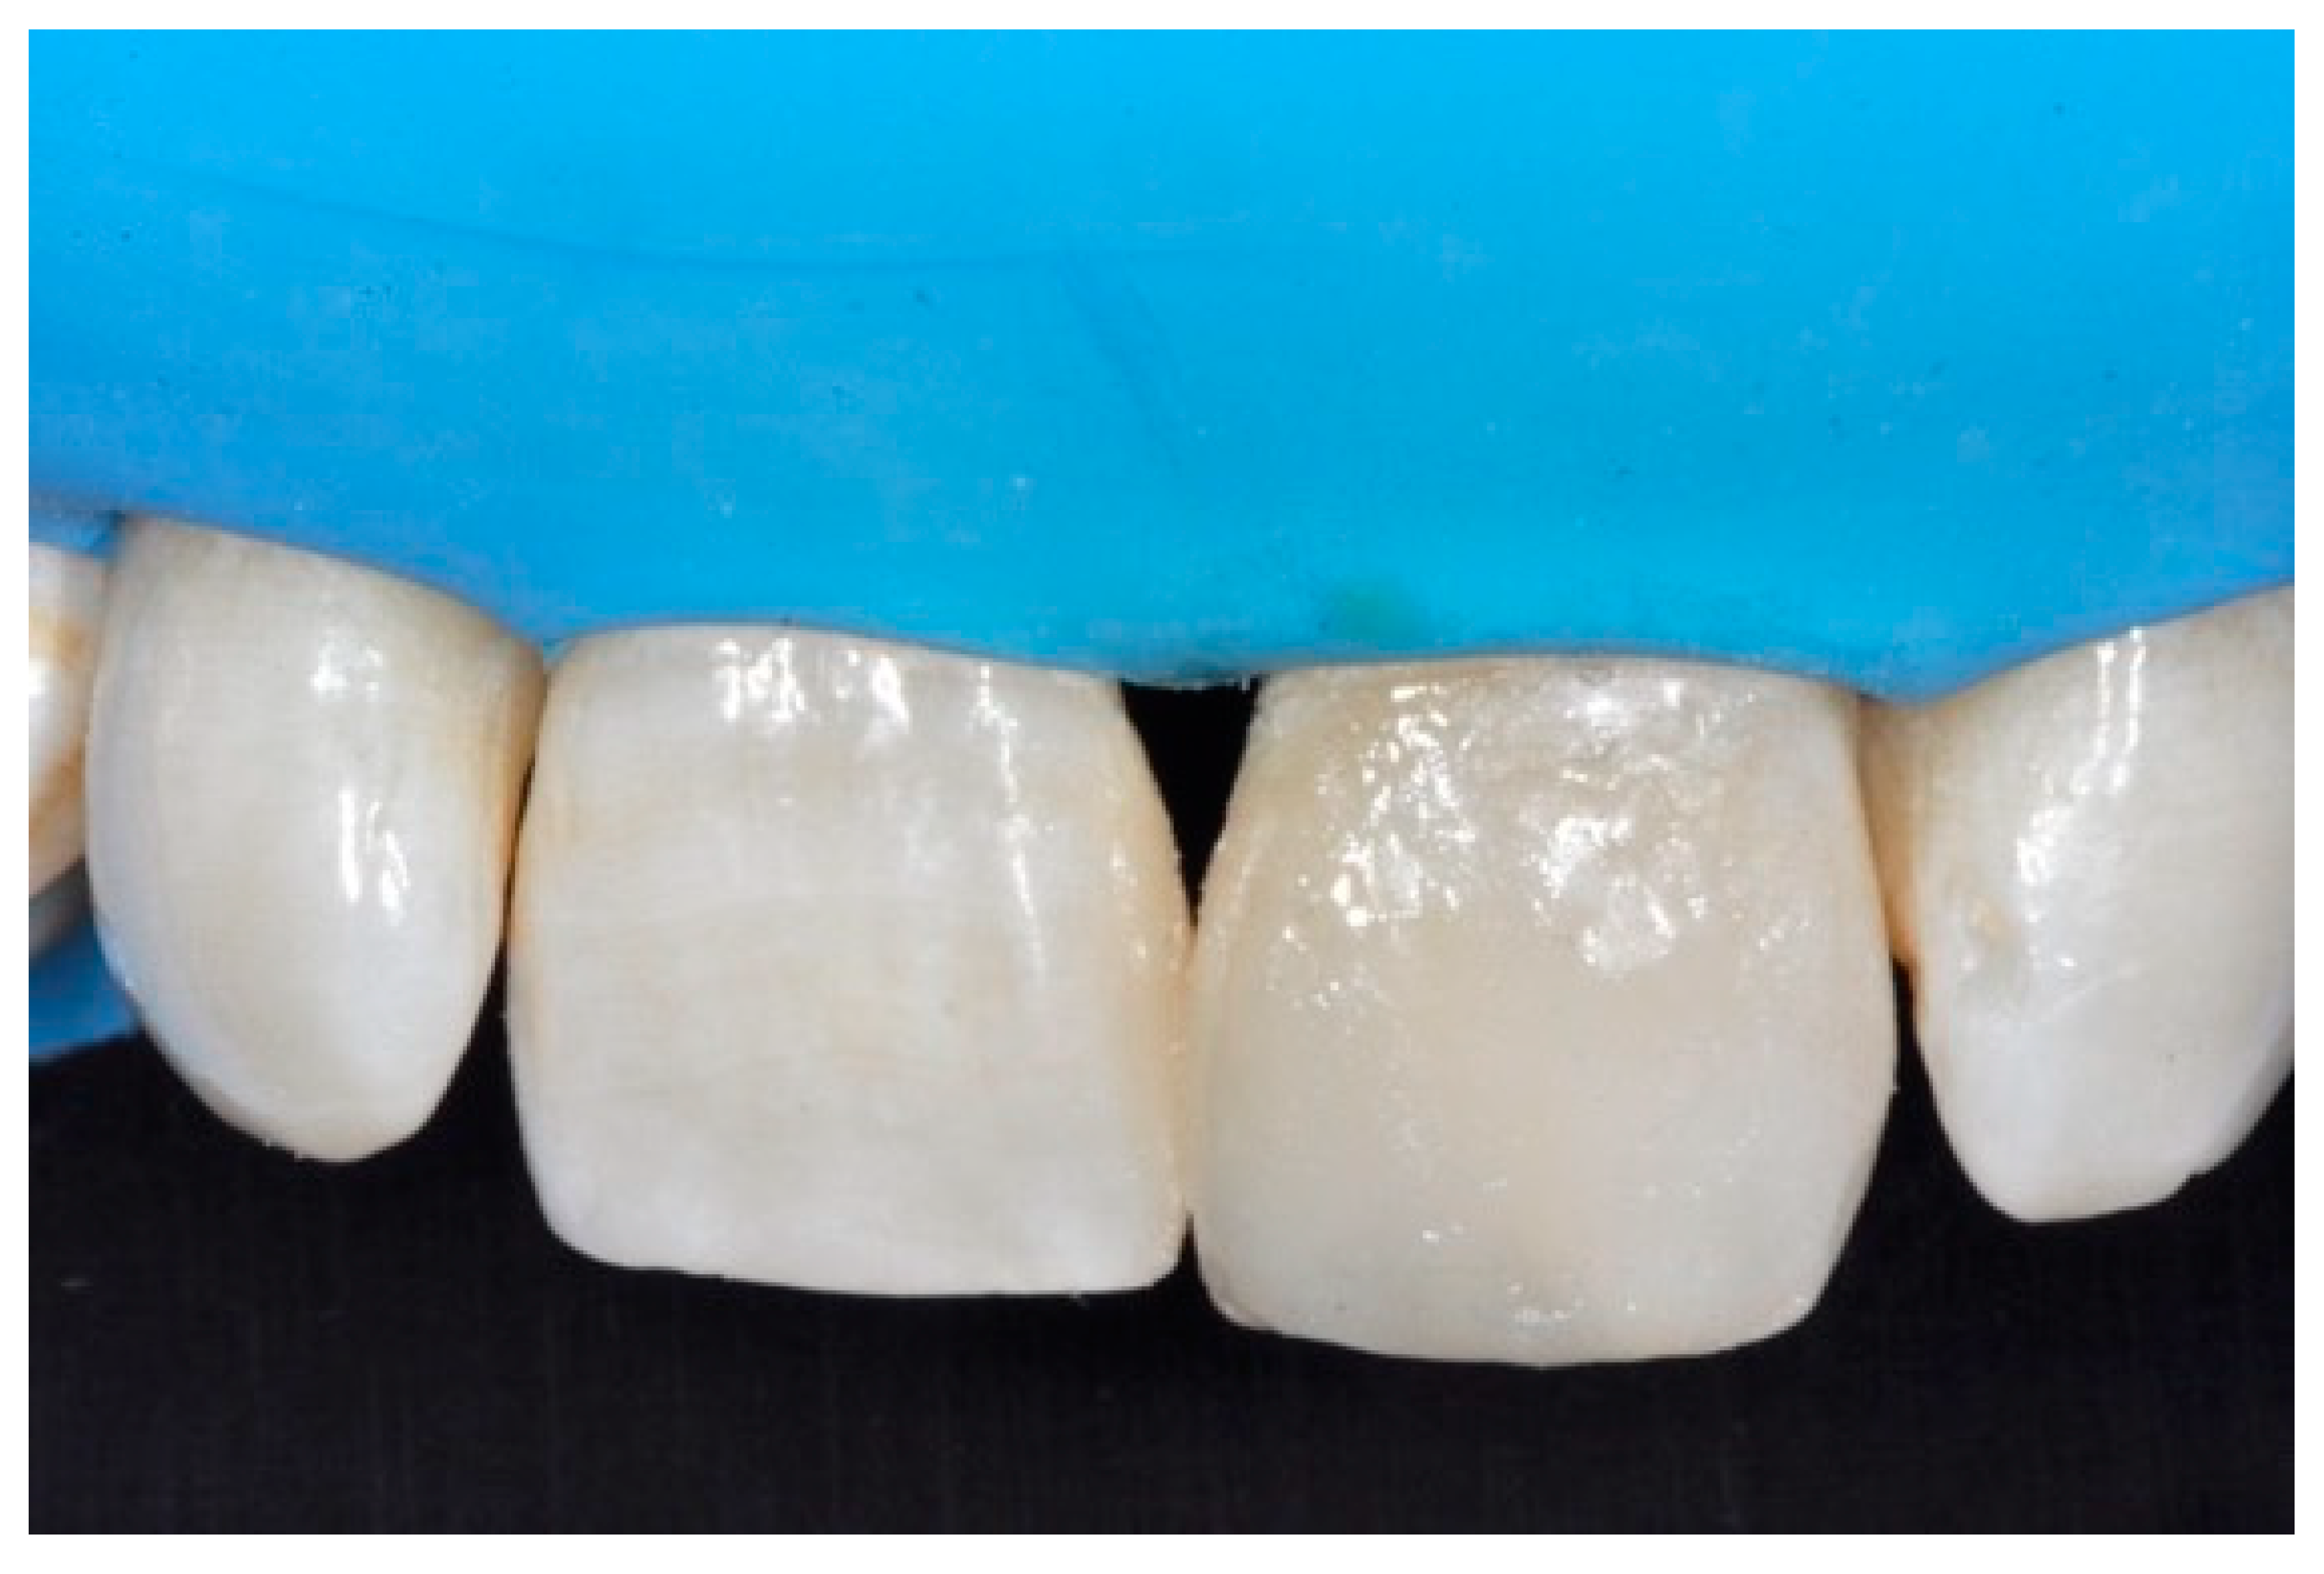

Once completed, the two frames (Clearfil Majesty ES-2, A1E, A2D, Kuraray Noritake Dental, Tokyo, Japan) showed internal and external excesses that were reduced using diamond burs and discs (Figure 33 and Figure 34) strictly following the procedure described in Section 2.1.2 of present article. Excesses were removed from the distal-incisal angle of #2.1 allowing therefore to obtain the desired translucency. After silane application and bonding procedure (Figure 35) as described in Section 2.1.2, restorations were completed (Figure 36 and Figure 37). They both show satisfactory clinical integration 1.5 years post-operative (Figure 38 and Figure 39).

Figure 38.

At 1.5 years, post-operative clinical view. Reprinted from Restauri diretti nei settori anteriori, G. Paolone, S. Scolavino, © 2021, with permission from Quintessence Publishing Italy.